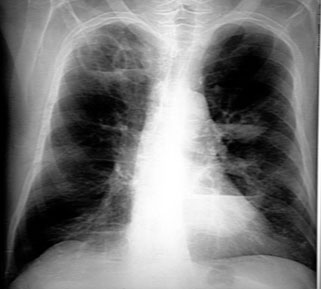

Each tissue reacts to injury in a predictable fashion. Multiple etiology can evoke a similar pathological reaction. Let us review the pathological process that can occur in the lung following lung injury. Lung injury can be either generalized or localized. The consequence of lung injury could either lead to a liquid or increased air density in CXR. There are radiological signs for each of the pathological process.